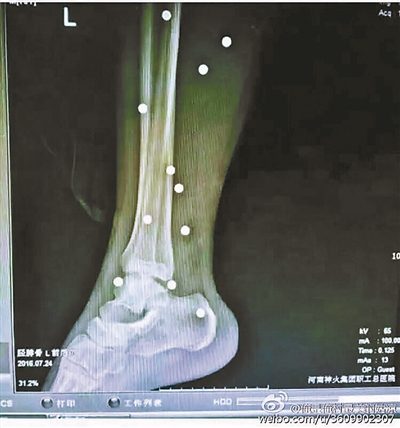

傷者體內(nèi)取出的鋼珠

爆炸導(dǎo)致鋼珠遍布傷者身體各處

黃明的伯伯對(duì)北青報(bào)記者表示,由于黃明直接踩到了爆炸物,所以傷情最為嚴(yán)重,“他的腿被炸斷,身體內(nèi)被炸進(jìn)了40多顆鋼珠。手術(shù)后已經(jīng)從體內(nèi)取出29顆鋼珠,還有十多顆鋼珠沒有取出來?!备鶕?jù)黃明的入院記錄,他全身有多處爆炸傷,且全身多處異物存留。

爆炸發(fā)生時(shí),陳浩的位置與黃明靠得很近,因此也受傷較重。他告訴北青報(bào)記者,經(jīng)過10多個(gè)小時(shí)的手術(shù)后,醫(yī)生從他身體里取出了12顆鋼珠。目前,他和黃明兩人經(jīng)過手術(shù)后,已從重癥監(jiān)護(hù)室轉(zhuǎn)至普通病房。其余三人中,陳剛的臀部受傷,當(dāng)天晚上在醫(yī)院清理完傷口后便回了家,而同行的兩名女生身上有一些擦傷。